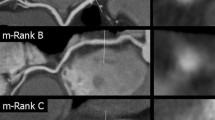

Non-calcified plaques were assessed quantitatively on an offline workstation (InSight, Neo Imagery, San Francisco, Calif.). The volumes of non-calcified plaques in the coronary artery wall were classified using thresholds of 0–130 HU. The outer border of the plaques was segmented manually, whereas the internal border between plaque area and contrast-enhanced vessel lumen was detected by the software and the plaque volume was calculated automatically (Fig. 1). The number, segmental location, and volumes of all non-calcified plaques, and the total non-calcified plaque volume burden per patient, were recorded.

Quantitative volumetry of non-calcified plaques. The quantitative volumetry was performed on an offline workstation (InSight, Neo Imagery, San Francisco, Calif.) The axial image at the height of the origin of the left coronary artery (left window) shows a large non-calcified plaque in the distal part of the left main coronary artery (arrow). Volumetry was conducted semi-quantitatively, segmenting the soft plaque borders by hand, whereas the software measured plaque volume automatically according to predefined thresholds (right window, see ellipsis for results)

According to the CT findings, the detected plaques were divided into three groups: purely calcified plaques (CP); mixed plaques (MP); and purely non-calcified plaques (NCP). Mixed plaques were defined as plaques with calcifications and non-calcified components in direct vicinity to each other. The quantification of non-calcified plaques was done only for the subgroup of patients, who presented real non-calcified plaques. In patients with mixed plaques, i.e., plaques consisting of calcified and non-calcified components, the volume of non-calcified plaque burden could not be assessed by the analysis software. The "total plaque volume", given in cubic millimeters, was defined as the sum of calcium volume equivalent and the volume of the non-calcified plaques.